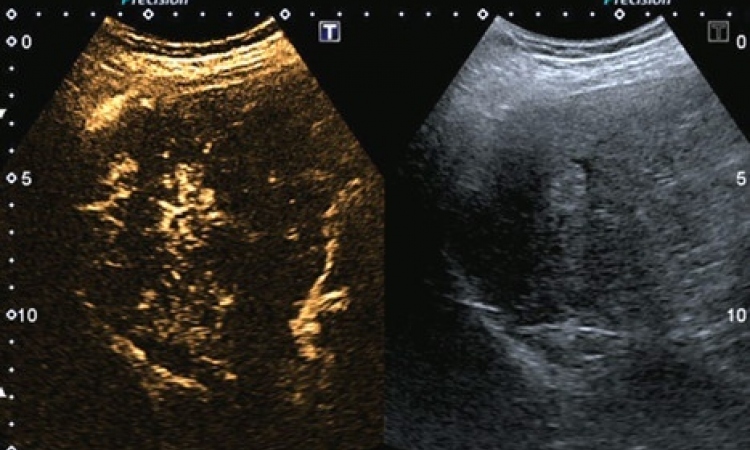

Abb. rechts: In der MRCP zeigt sich eine Kompression des Pankreasganges durch den Tumor (Pfeil) und die periphere Gangerweiterung (gestrichelte Pfeile).